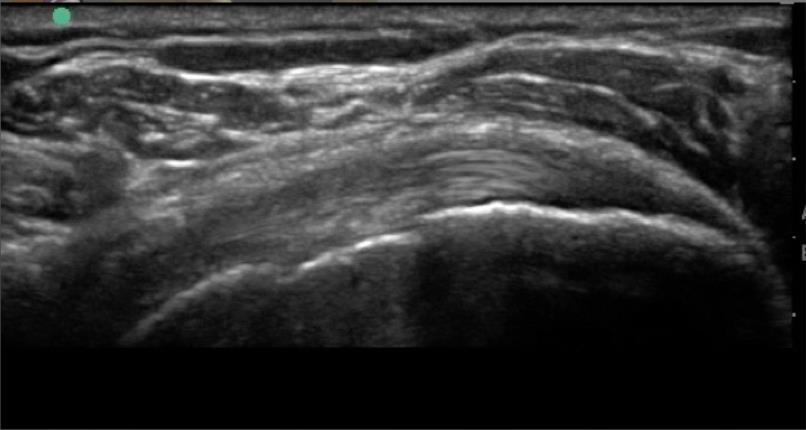

Shoulder Infraspinatus Tendon – Long Axis Enthesis 3 Image